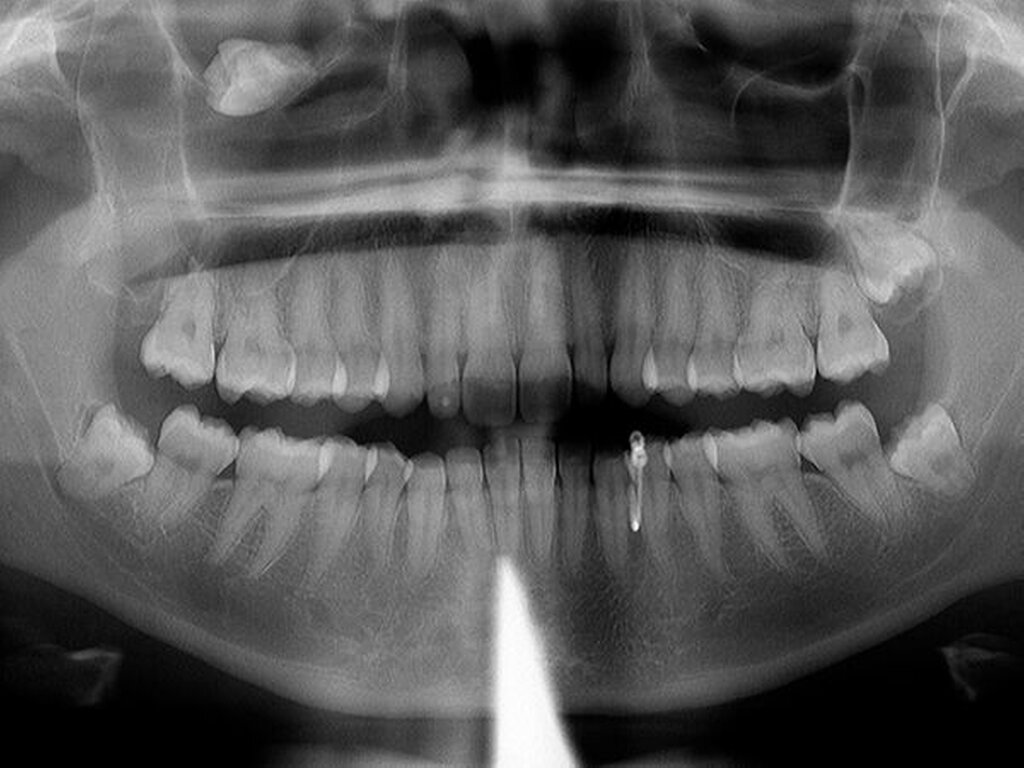

Nach erfolgtem Eingriff unter stationären Bedingungen konnte die Nachbehandlung ambulant in unserer Praxis erfolgen und gestaltete sich im wesentlichen störungfrei. Die Röntgenkontrolle nach vier Jahren zeigte operationsbezogen einen Normalbefund (Abbildung 4): Kieferhöhlen rechts und links (soweit beurteilbar) lufthell, Zähne 28, 38, 48 in etwa orthograd (also: Verlaufsbeobachtung vertretbar).

Die anderen Zähne im I. Quadranten blieben vital, die infraorbitale Sensibilität hatte sich innerhalb kurzer Zeit (Wochen) normalisiert, die Doppelbilder waren verschwunden. Die Patientin äußerte sich im weiteren Verlauf sehr zufrieden über Diagnostik und Therapie. Sie hatte auch keine Beschwerden mehr verspürt. Die Zähne 28, 38, 48 wollte die Patientin bis heute nicht entfernen lassen.